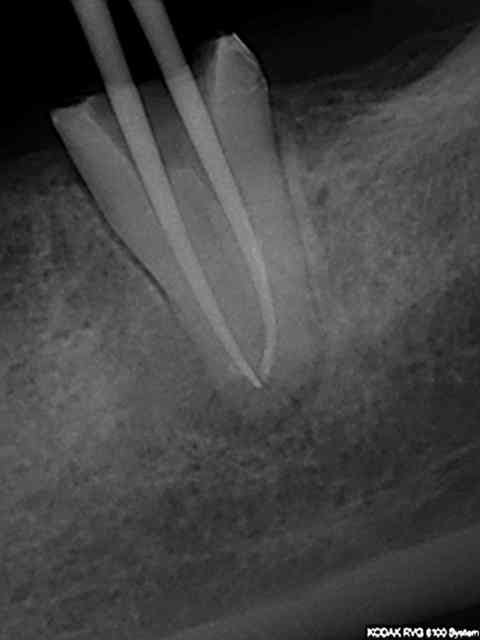

J'utilise le système heroshaper+digue+hypo+condensation

Mac Spadden(thermomécanique)

J'ai posté des radios biopulpectomies et retraitements

canalaires précédemment.

L'obturation 3D est indispensable pour un traitement hermétique.Mon associé utilise le système protaper et

effectivement cela élargit plus.Sur ces 7 dernières années

j'obtiens de bons résultats;mon avis le système heroshaper

casse moins mais n'hésite pas à jeter un heroshaper

même si non déspiralé ;si il a travaillé un peu en force

ou si la morphologie canalaire est un peu compliquée ou courbe;on fait un peu un usage unique pour éviter tout

problème plus tard!(quelque soit le système)on récapitule

avec un instrument à mains;pour une bonne herméticité

le système Mac spadden est le plus efficace ,utlisé par des endos exclusifs,et le moins cher (un cone de gutta est suffisant)Ma séquence classique instrument à main N10

héroshaper N20 6%/4% N25 4% N30 4% MAC SPADDEN un cone de gutta/ciment sealite régular

J'ai reposté quelques radios de biopulpectomies

RTE dans un précédent post...